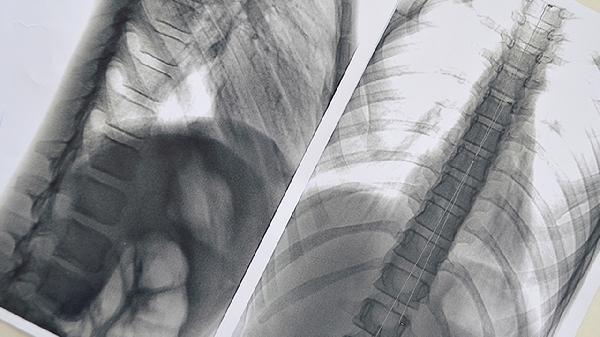

肺部有实性结节是怎么回事,要紧吗

肺部有实性结节可能是炎症、结核、良性肿瘤或恶性肿瘤等引起的,多数情况下属于良性病变,但需要定期随访观察。实性结节的处理方式主要有定期复查胸部CT、穿刺活检、手术切除等。建议及时就医,由医生根据结节的大小、形态、生长速度等特征评估风险。